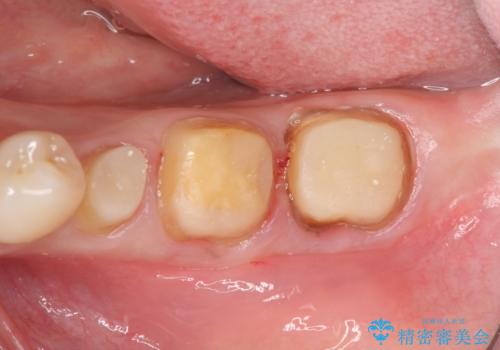

- 左下の歯が虫歯により崩壊し、歯ぐきからの出血も毎回歯ブラシを行う際に出ることから治療を求めて来院されました。

現在装着されているクラウンを除去したところ、クラウンマージンが歯肉縁下となり歯ぐきの炎症が認められたため再度オールセラミッククラウンを製作する前に歯周外科手術を行い歯ぐきの状態を改善しました。